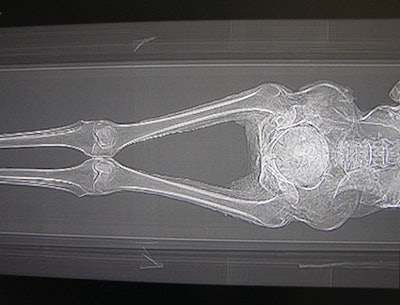

![]() |

| Above: The thoracic and pelvic regions of the mummy. Below: A lateral view of the regions. Bottom: The pelvis and legs. Images courtesy of Michelle Cotton, Advanced Radiology Consultants. |

One of the most surprising findings on the CT data is that the mummy appears to be female due to its pelvic structure and signs of arthritis in the area, a possible indication of having given birth, according to experts at Advanced Radiology. Despite the findings contradicting the long-held belief that the mummy was male, the remains could still be those of an Egyptian priest as claimed, as women also held that position, according to Barnum Museum's executive director and curator Kathy Maher.